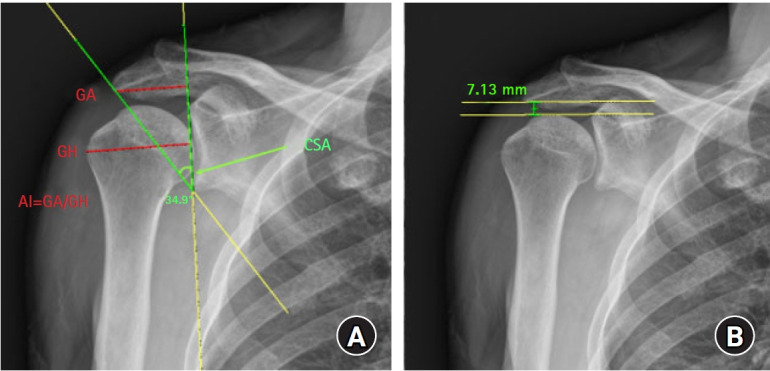

Pre- and postoperative standard radiographs of the shoulder (anteroposterior [AP], true AP, scapular Y, and axillary views) were evaluated. Two orthopedic physicians (MSJ and KLK) independently reviewed the preoperative radiographs to assess the CSA, AI, and acromiohumeral interval (Fig. 2). The CSA was measured as defined by Moor et al. [18], using a line connecting the superior and inferior bone margins of the glenoid and an intersecting line drawn from the inferior bone margin of the glenoid to the most lateral border of the acromion. The AI was measured as the value obtained by dividing the distance from the glenoid plane to the lateral border of the acromion by the distance from the glenoid plane to the lateral aspect of the humeral head. The acromiohumeral interval was measured as the shortest distance from the inferior surface of the acromion to the superior aspect of the humerus in the true AP view [19]. When a subacromial spur was present, the shortest distance between the spur and humeral head was measured.

Fig. 2.

Measurement of critical shoulder angle (CSA), acromial index (AI), and acromiohumeral interval (AHI) on anteroposterior shoulder radiographs. (A) CSA is formed by a line connecting the inferior with the superior border of the glenoid fossa and another line connecting the inferior border of the glenoid with the most inferolateral point of the acromion. AI is the distance from the glenoid plane to the lateral border of the acromion (GA) divided by the distance from the glenoid plane to the most lateral aspect of the humeral head (GH). (B) AHI is measured as the shortest distance from the inferior surface of the acromion to the superior aspect of the humerus.